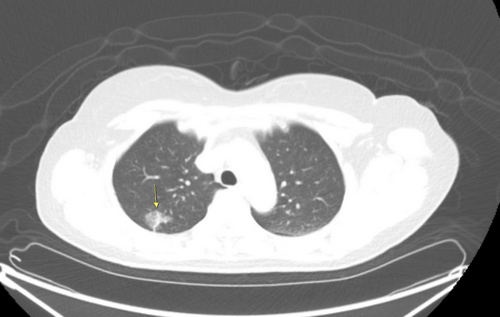

徐中平副院長說,目前肺癌病例近七成是肺腺癌,共同點是沒有明顯症狀。有些病灶的電腦斷層影像看起來像是毛玻璃的灰影(箭頭所指處),如果病灶小於1公分,且無實心變化,就可能是癌前病變或原位癌。(徐中平提供)

肺癌病人早期幾乎沒症狀,而腫瘤只要達1公分就可能轉移。若已出現咳嗽、咳血、喘、疼痛、體重減輕等症狀時,多已經到晚期。徐中平副院長指出,經低劑量電腦斷層檢查發現如毛玻璃霧面狀病灶,就需要定期追蹤。若超過0.8公分或質地較扎實,則病灶有可能已癌化。如情況許可手術切除為第一選擇,其他尚有放射線治療、化學治療、標靶治療、免疫治療等各種療法。其中標靶治療與免疫治療須先做基因檢測,有特定基因表現才適用,而健保對符合條件的病患也會給付。

徐中平副院長說,目前肺癌病例近七成是肺腺癌,共同點是沒有明顯症狀。有些病灶的電腦斷層影像看起來像是毛玻璃的黑影,這可能是癌前病變或原位癌;有些病灶則看起來較扎實,那就有可能是較具侵犯性的腫瘤。花蓮慈院10年前將LDCT納入同仁健檢項目,也因此有許多同仁發現早期肺癌即時手術治療,都有良好的治療結果。 早期花蓮慈院收案的肺癌病人多是在第3-4期,只有30%是屬於癌症0-2期可開刀治療病人;近年政府推動低劑量電腦斷層肺癌篩檢,可開刀病人已經提升到近五成。徐中平副院長提醒,50歲以上的重度吸菸者、或45歲以上有家族病史的高危險群,憑健保卡每二年可定期接受國家補助的低劑量電腦斷層免費肺癌篩檢,以確保肺部安康。